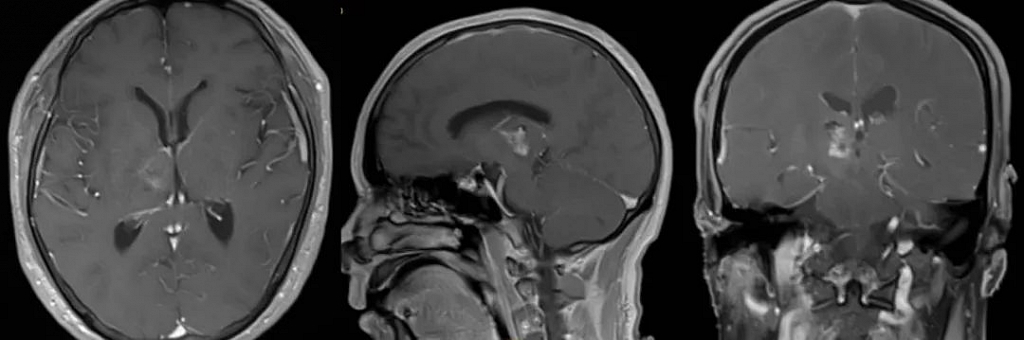

术前影像

桂林医学院第二附属医院神经外科对莫先生进行了详细的检查。住院观察期间,莫先生症状加重,头晕头痛明显,左侧肢体有明显偏瘫现象,且频繁昏睡,瞳孔扩大,术前处于昏迷状态。医生结合莫先生病史、症状以及CT检查等表现,诊断其为右侧丘脑脑脓肿。

复查影像

近日,莫先生回到医院复查,头颅磁共振提示脑脓肿消失、只剩下癍痕病灶,身体康健的他为神经外科治疗团队献上锦旗,感谢医护人员的精准诊治。